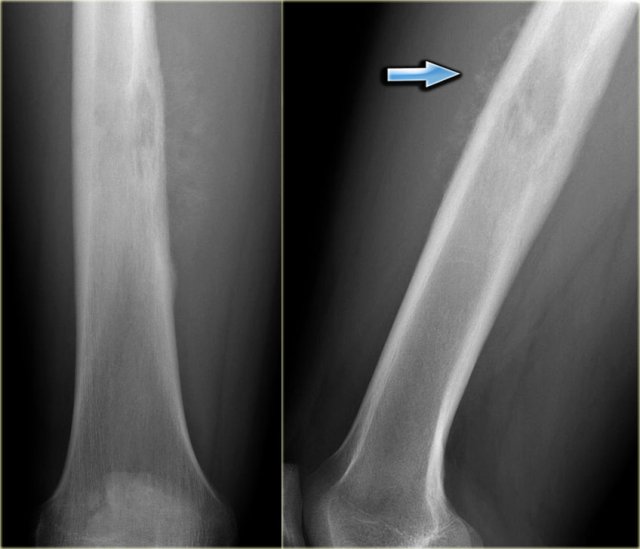

ABC versus Adamantinoma. Notice resemblance between intracortical ABC in tibia (left) and Adamantinoma (right). ABC versus Adamantinoma. Notice resemblance between intracortical ABC in tibia (left) and Adamantinoma (right).

ABC (6) - atypical case

On the left two different patients with an intracortical or subperosteal osteolytic well-defined lesion in the tibia.

The lesion on the far left was thought to be an adamantinoma because of the localisation in the anterior tibial cortex.

At biopsy it proved to be an ABC.

The image on the right is an adamantinoma.